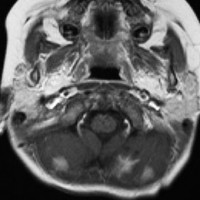

3歳発症の髄芽腫です。M2/M3でしたから,生検術などせずに,脳室ドレナージをして,ICE化学療法で治療を開始しました。

化学療法を開始して21日目のMRIです,腫瘍はかなり小さくなっています。この後に,手術摘出(病理確定)や脳脊髄照射などをしました。この例はいずれにしても化学療法をする必用があったものです。